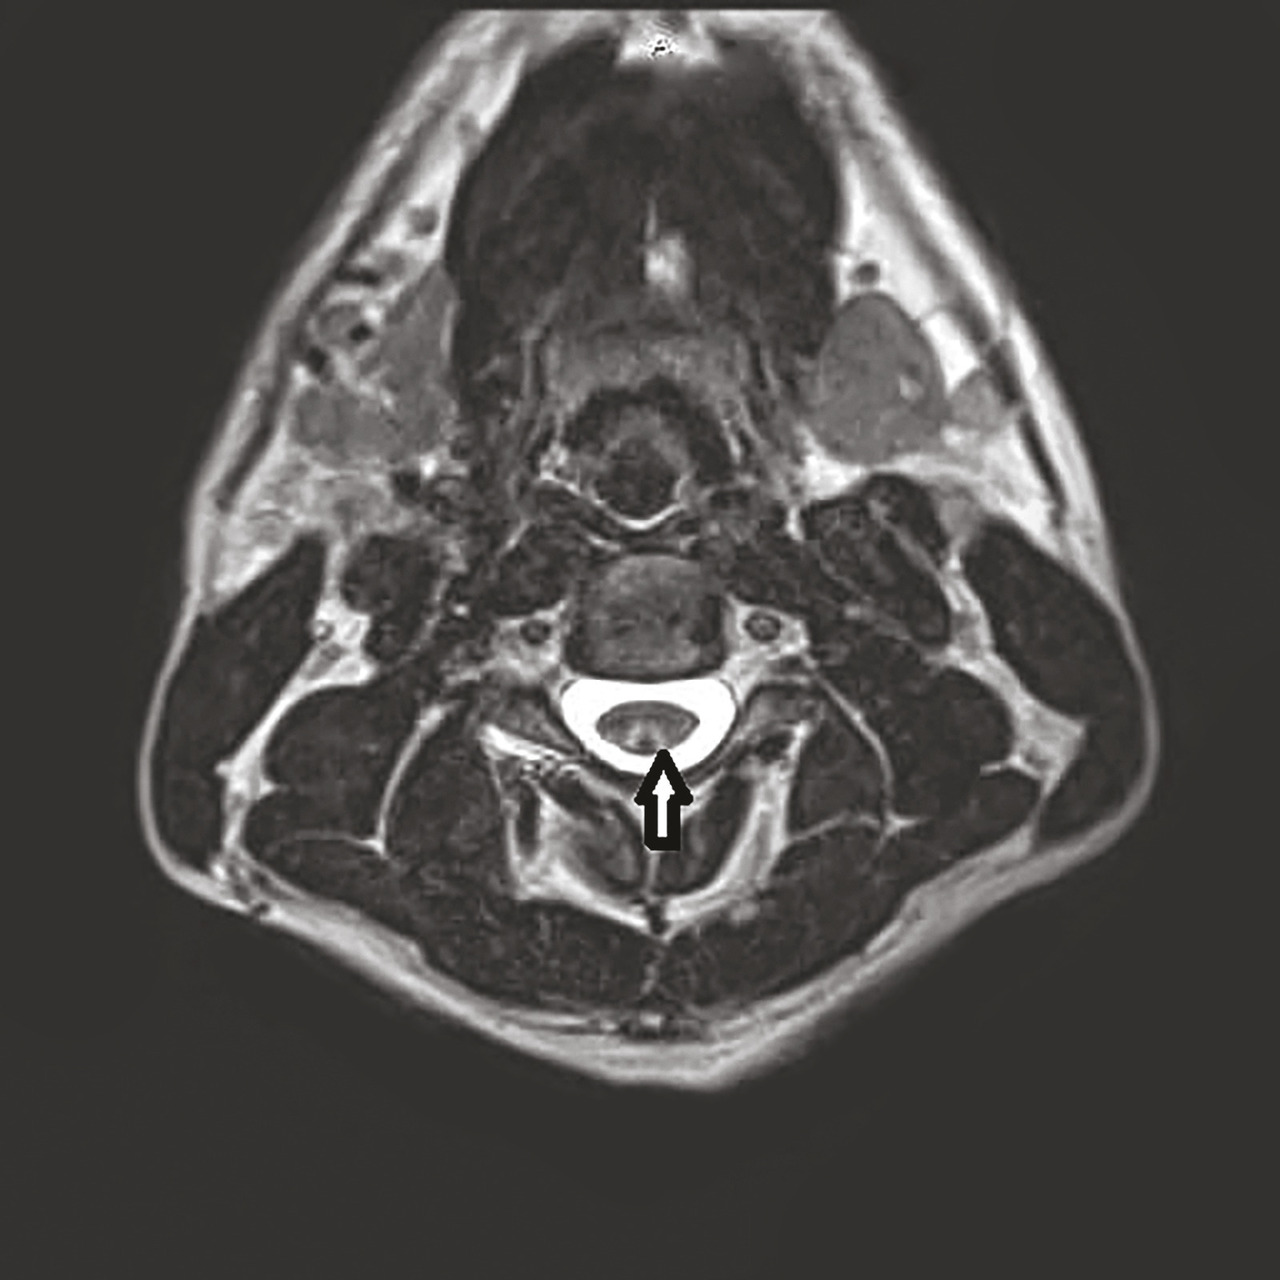

Cet homme de 36 ans, sans antécédent particulier, consultait pour des sensations de peau cartonnée aux pieds et aux mains évoluant depuis trois semaines. Il rapportait la consommation journalière depuis un mois de 40 ballons de protoxyde d’azote (NO). L’examen notait la présence d’un signe de Lhermitte déclenché par l’antéflexion céphalique, des réflexes ostéotendineux vifs et symétriques, une apallesthésie des membres inférieurs et une sensibilité superficielle préservée, sans déficit moteur associé. Le bilan biologique montrait un déficit en vitamine B12 à 179 pg/mL (211-911) et une homocystéinémie supérieure à 50 µmoles/L (5-15). L’IRM cervicale montrait une lésion médullaire postérieure étendue, localisée aux cordons postérieurs (fig. 1 et 2 ).